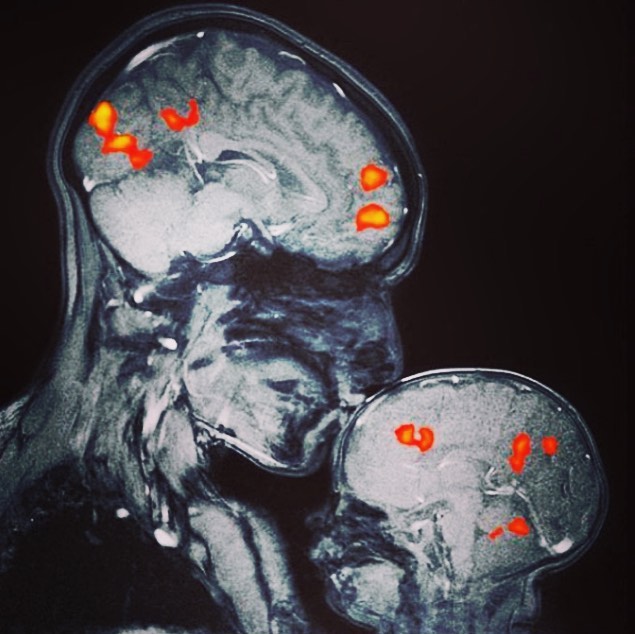

Se trata de la primera imagen en resonancia magnética que muestra la actividad cerebral del vínculo afectivo entre madre e hijo, tomada por la neurocientífica Rebecca Saxe mientras besa a su hijo de dos meses.

Las señales coloreadas destacadas en la resonancia se refieren a la actividad cerebral que se activa durante este sencillo pero a la vez complejo acto de amor: el beso